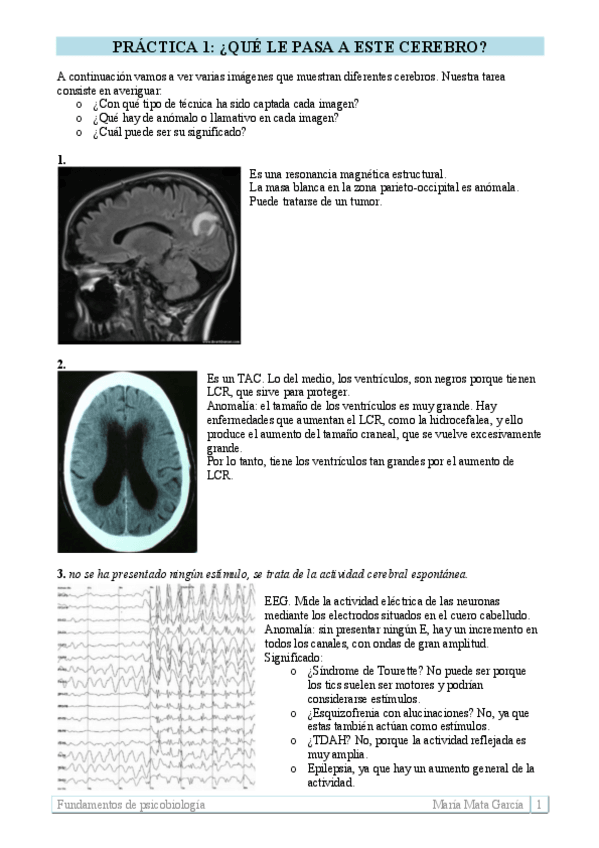

Práctica 1 - Bloque I